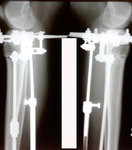

на фиксации